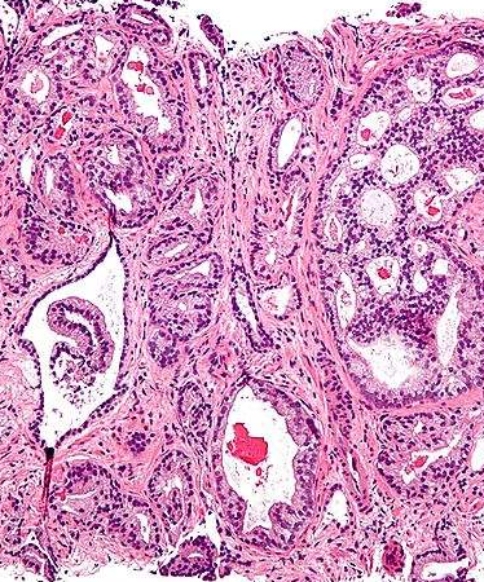

乳腺癌是女性較高發(fā)的惡性腫瘤,乳腺癌早期治療預(yù)后好,如果到了晚期,則沒有太好的治療方法,近幾年的乳腺癌靶向治效果果比較好,人們對(duì)乳腺癌靶向治療也寄予了厚望,日本開始探索新一代乳腺癌靶向藥

具有競爭/拮抗活性的選擇性雌激素受體調(diào)節(jié)劑(SERM))具有比較好的治效果果和治療優(yōu)勢(shì),特別是對(duì)絕經(jīng)前期乳腺癌。雖然已經(jīng)在雌激素受體α(ER)和共激活因子的動(dòng)態(tài)關(guān)系以及和生長因子信號(hào)的對(duì)話中研究了這些調(diào)節(jié)劑的作用效果,但是其中的分子基礎(chǔ)仍然不是特別清楚。較近來自日本東京大學(xué)的研究人員對(duì)SERM的作用機(jī)制進(jìn)行了更深入的探討,相關(guān)結(jié)果發(fā)表在國際學(xué)術(shù)期刊JCI上。

在這項(xiàng)研究中,研究人員發(fā)現(xiàn)了一系列控制ER和共因子動(dòng)態(tài)性以及SERM功能的調(diào)控機(jī)制,他們還發(fā)現(xiàn)SERM活性發(fā)揮需要Fbxo22的參與。SCF Fbxo22能夠?qū)嚢彼崛ゼ谆?B(KDM4B)進(jìn)行泛素化,而在發(fā)生泛素化之前KDM4B與結(jié)合了他莫昔芬的ER形成復(fù)合體的,KDM4B的降解能夠從ER復(fù)合體上釋放除類固醇受體共激活因子(SRC)。

研究表明敲除Fbxo22會(huì)通過AF1導(dǎo)致ER依賴性轉(zhuǎn)錄激活,甚至在SERM存在的情況下也會(huì)發(fā)生。研究人員在活細(xì)胞中發(fā)現(xiàn),他莫昔芬通過Fbxo22依賴性方式從ER復(fù)合體上釋放SRC和KDM4B,并且在幾乎所有ER-SRC結(jié)合的增強(qiáng)子和啟動(dòng)子上,他莫昔芬誘導(dǎo)SRC的釋放需要Fbxo22的參與。他莫昔芬無法阻止缺失Fbxo22的ER陽性乳腺癌生長,無論是在體外還是在體內(nèi)均是如此。

研究人員又進(jìn)一步在臨床樣本中進(jìn)行了分析,他們發(fā)現(xiàn)腫瘤組織中Fbxo22的低水平表達(dá)可以在高風(fēng)險(xiǎn)比的ER陽性HER2陰性的乳腺癌中預(yù)測(cè)更差的臨床結(jié)果,并且還獨(dú)立于Ki-67等其他標(biāo)志物。該研究提出根據(jù)腫瘤組織中Fbxo22的水平可以定義一個(gè)新的ER陽性乳腺癌亞型,SCF Fbxo22介導(dǎo)的KDM4B降解可以成為下一代SERM的治療靶點(diǎn)。